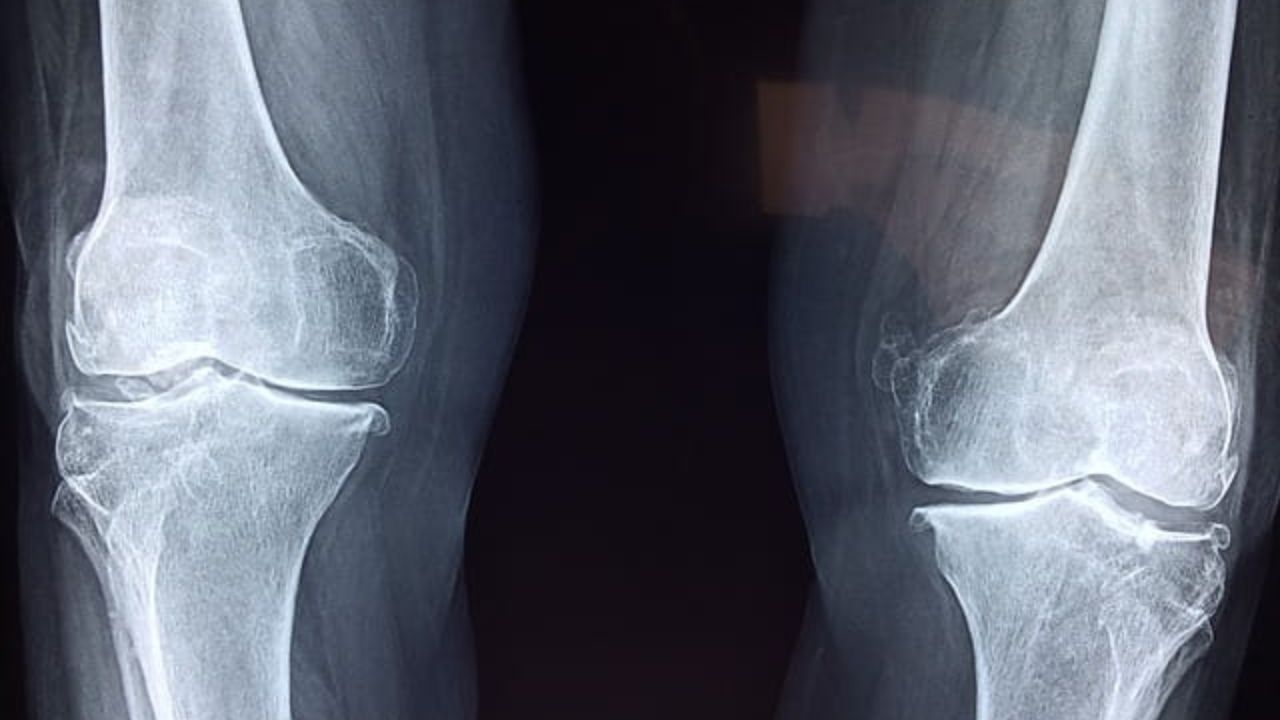

O diagnóstico é realizado pelo ortopedista através do exame clínico e testes de compressão patelar. Radiografias simples com incidências específicas (perfil e axial de patela) costumam revelar a diminuição do espaço entre os ossos e a presença de osteófitos (bicos de papagaio). Em fases iniciais, a ressonância magnética é o exame de escolha, pois consegue detectar o amolecimento da cartilagem antes mesmo dela desaparecer por completo, permitindo uma intervenção mais precoce.